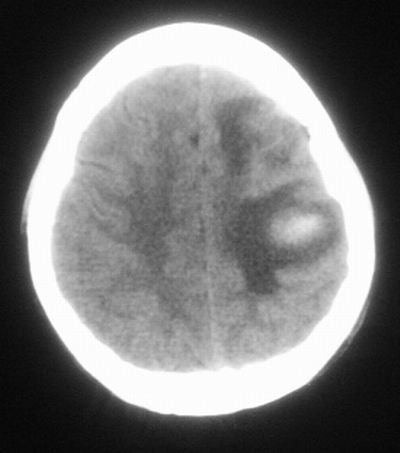

治疗三天后复查ct片示:

治疗三天后复查ct:除左侧额顶叶血肿外。左侧额叶另见片状低密度灶,密度不均匀,境界不清;考虑脑梗塞。

左侧额顶叶血肿伴出血后梗塞!

左侧额顶叶脑出血伴出血后脑梗塞